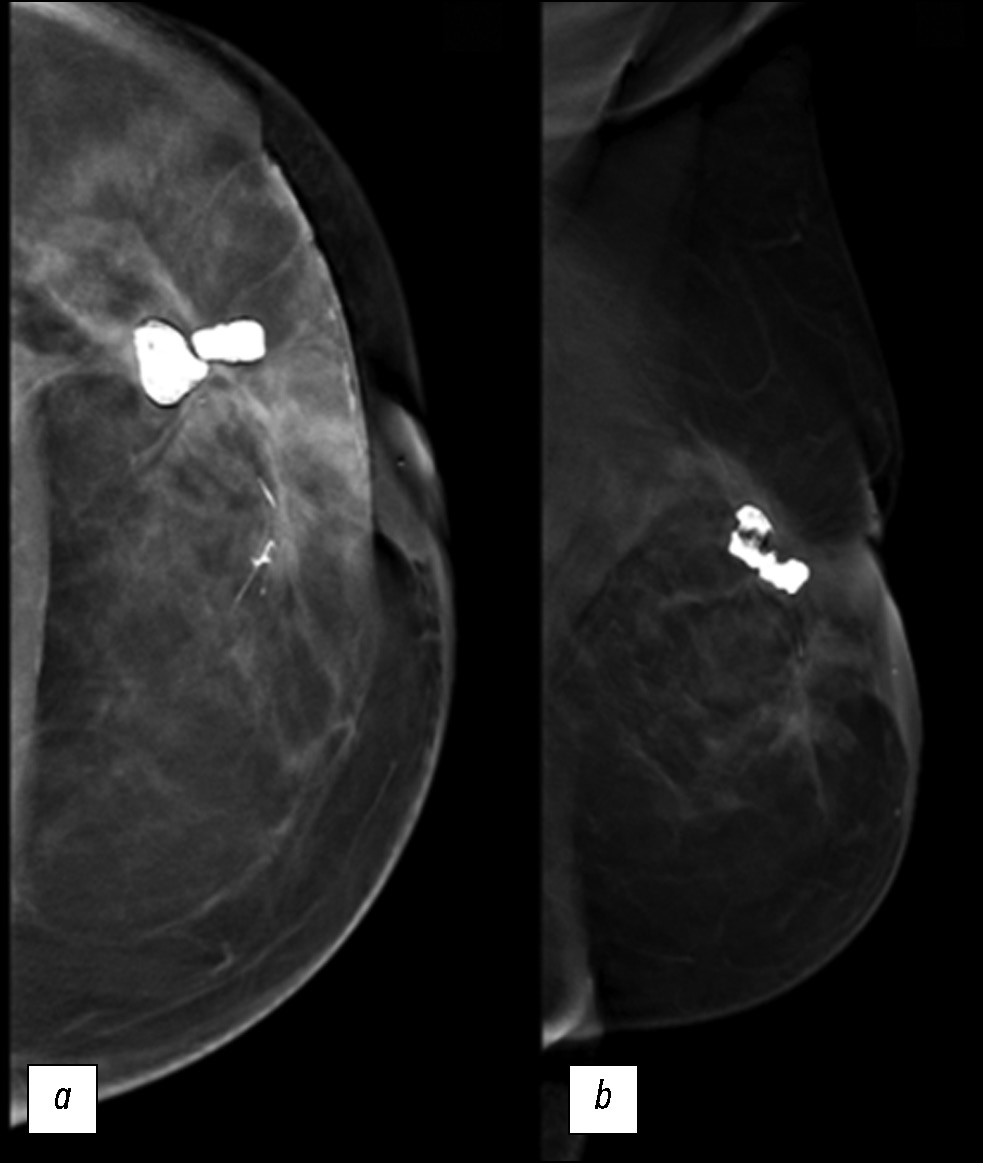

В настоящей статье описан редкий случай вторичной ангиосаркомы молочной железы у 72-летней женщины с раком молочной железы в анамнезе. Пациентка обратилась в нашу клинику с безболезненным пальпируемым образованием в верхнем наружном квадранте левой молочной железы и прошла комплексное диагностическое обследование, которое включало консультации маммолога, патологоанатома и онколога. С помощью инструментальных методов диагностики, а именно маммографии, ультразвукового исследования и магнитно-резонансной томографии, удалось оценить степень распространённости опухоли, поражение лимфатических узлов и наличие отдалённых метастазов. Результаты биопсии ткани подтвердили диагноз. Основная цель рассмотрения этого редкого случая в настоящей статье является образовательной и состоит в описании клинической картины и комплексной диагностики заболевания, а также в обсуждении дифференциальных диагнозов и тактики его лечения. Вторичная ангиосаркома молочной железы — редкое и агрессивное новообразование, и для принятия корректных клинических решений и улучшения исходов у пациентов необходимо понимать его уникальные особенности. Для опухоли характерен менее благоприятный прогноз по причине её выявления на поздней стадии, повышенного риска быстрого образования отдалённых метастазов и ограниченного выбора вариантов лечения. В таких случаях требуются тщательное наблюдение за состоянием пациента, агрессивные тактики лечения и паллиативная помощь.